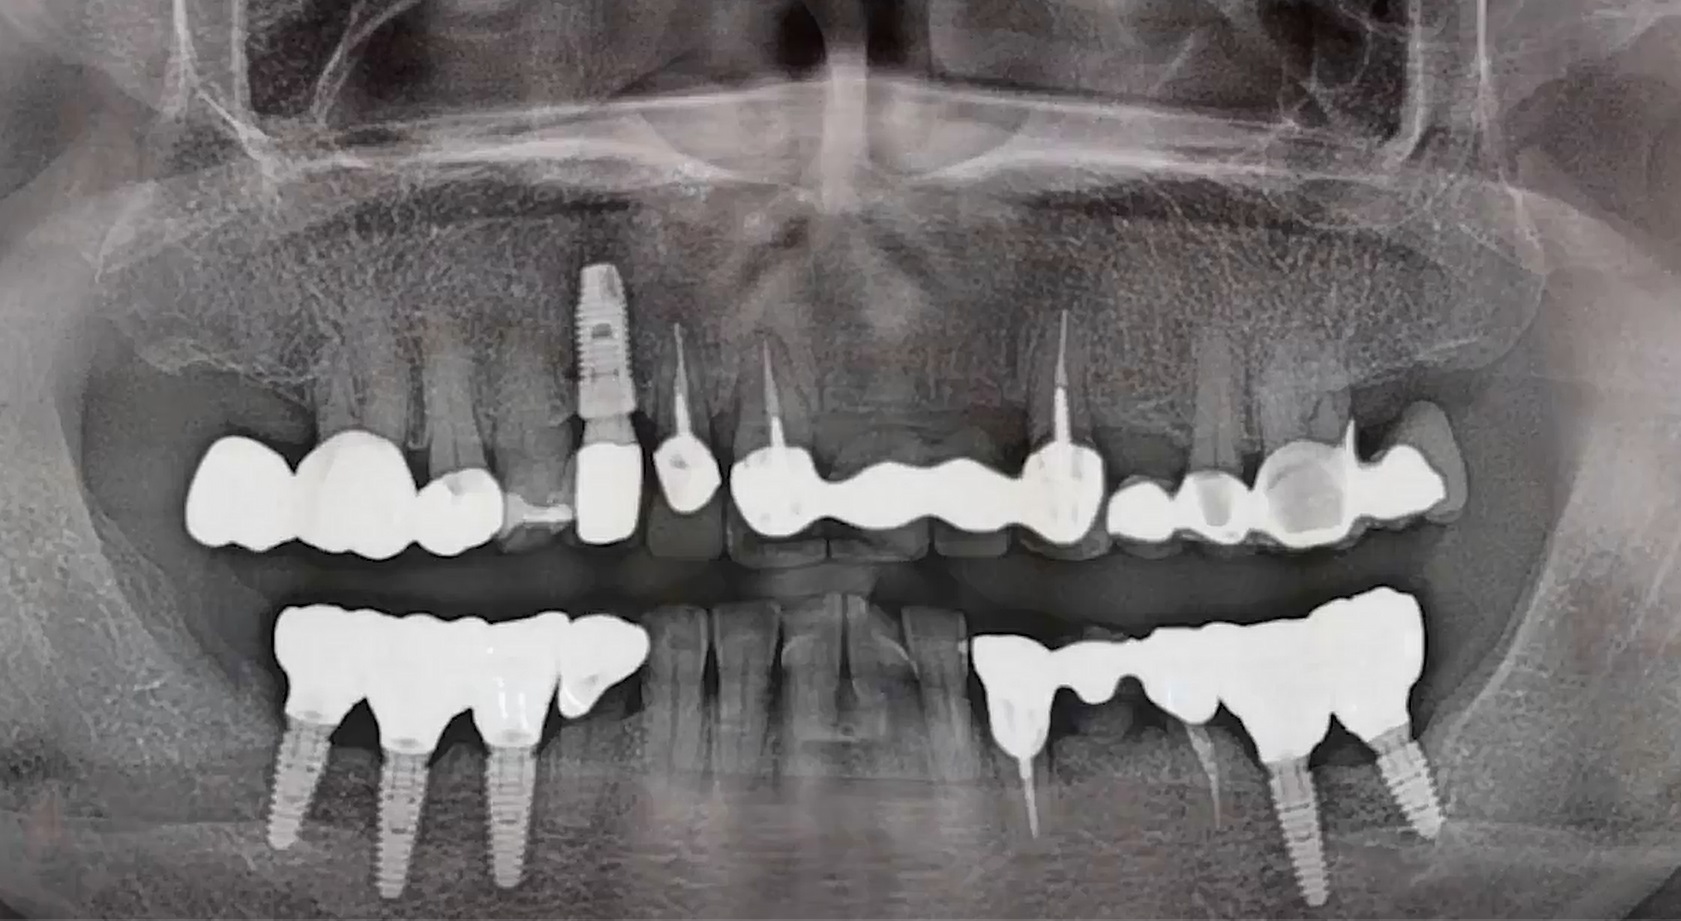

1 6 7 8